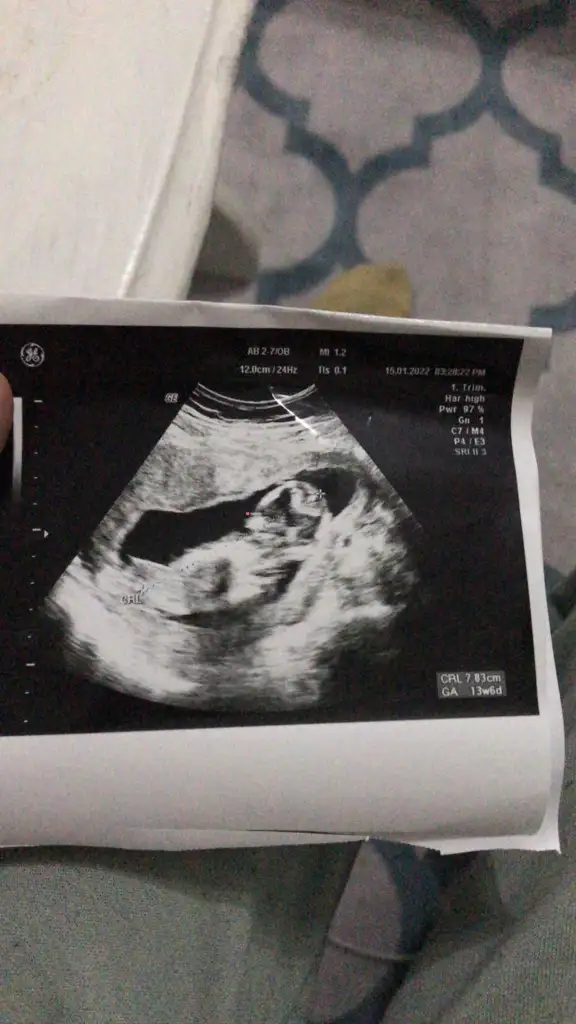

Burnu arıyoru o bi çıkıntı var orası mı acaba ay seni de rahatsız ediyorum amaBu sanirim 13 haftalikken daha önceki bi ultrasom burda sirti asagida sirt üstü yatmiş pozisyonda yani. Kafası yine sağ tarafta.

Daha kücük oldugundan burun ince minnak kirmzi nokta koydum burnun ucunaBurnu arıyoru o bi çıkıntı var orası mı acaba ay seni de rahatsız ediyorum ama

Ortadaki beyazlık kısımda buruna giden bölüm..zaten bu haftalarda ultrasonda kaliteli olmayınca gözükmezYok kız belli yaişte sırtı yukarda ağzıda belli